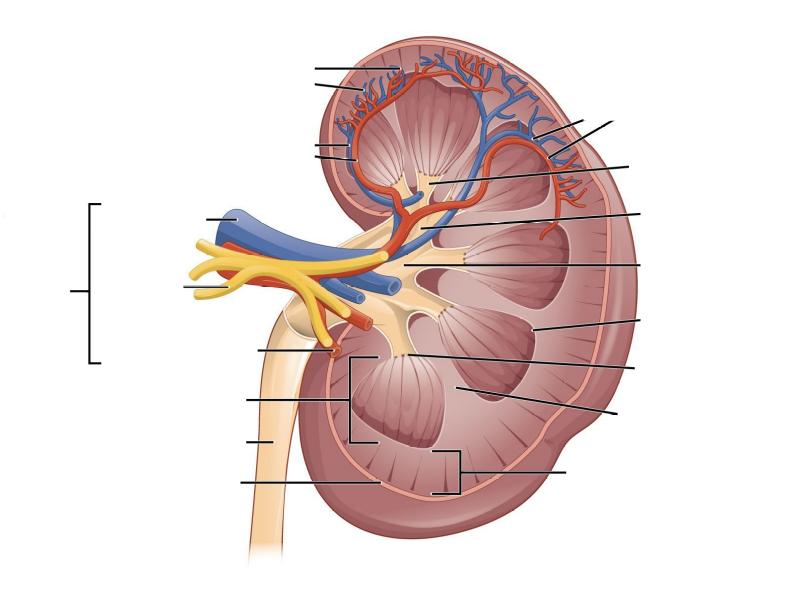

- Make an annotated drawing of the macroscopic view of the kidney.

- Make an annotated diagram of a nephron, including the juxtaglomerular apparatus. Indicate the flow of blood and water in each part, and how solutes are filtered, secreted and reabsorbed.

- Complete the drawings for each slide in the practical workbook.

Macroscopic

Anatomy

Of the

Kidney